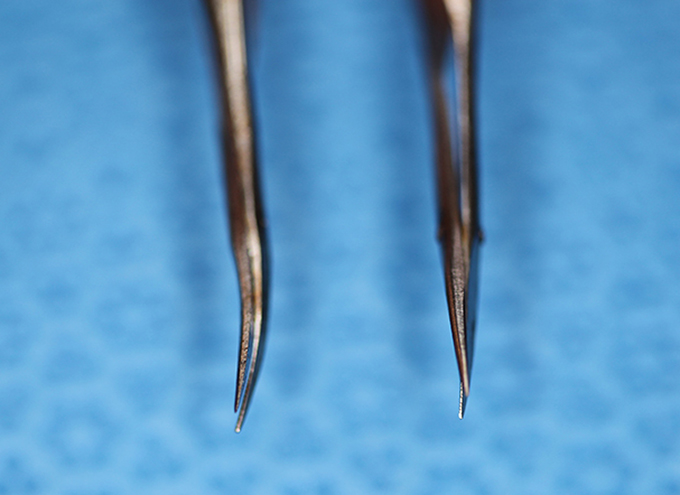

McPherson Angled Tying Forcep vs. Kellman McPherson Angled Tying Forcep

Typical Use(s): Tying suture

Forcep Thumb, Kellman-McPherson Angled T

(aka Kellman's forceps)

catalog number: Katena K5-5030

Typical Use(s): Very useful instrument; Substitute for angled tie; Removing material from AC

Forcep Thumb, Kellman-McPherson Angled T (Enlarged)

(aka Kellman's forceps)

catalog number: Katena K5-5030

Typical Use(s): Very useful instrument; Substitute for angled tie; Removing material from AC